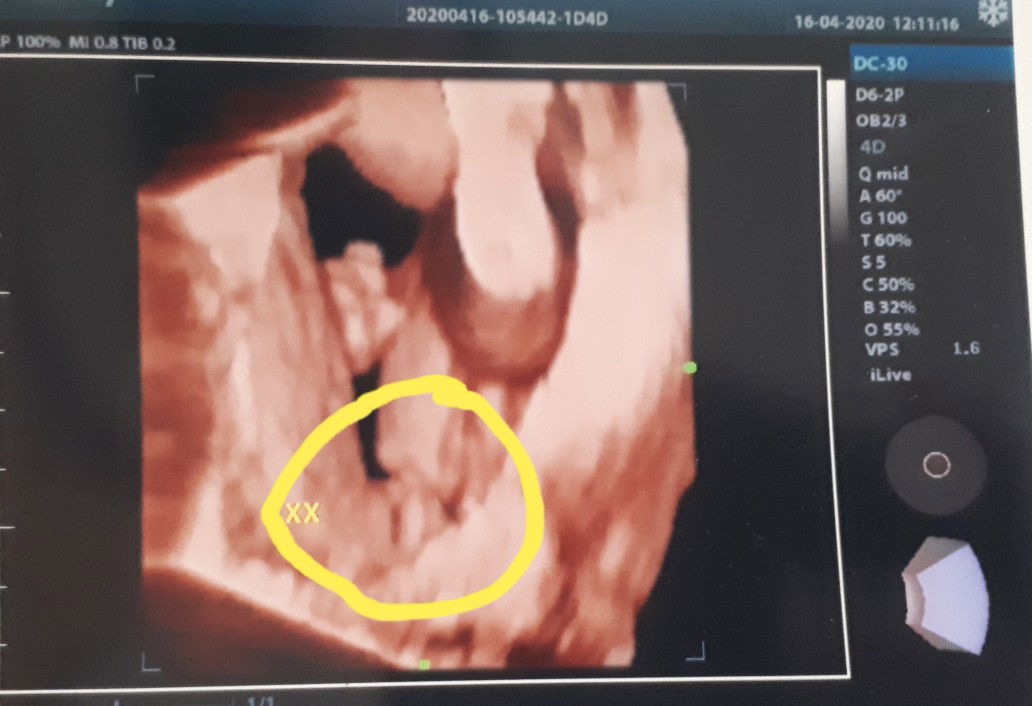

boy or girl

Hai mummy semua...tgk boy ke girl?? Ank ke 3... No 1 & 2 boy

Dktor ckp apa?? Boy ke girl . Tp mcm girl je sbb dktor tlz situ XX. XY bru laki😆😂 entah sy agak2 je hahaha.

Kt situ tulis xx.,.girl laa tu..lhipon nmpk mcm burger je☺️

Baby girl...nampak cam bentuk burger,doc bgitau sy😁😁

XX tu dia tulis..girl la tu.. Tahniah👏

Dy pin xx tu girl lh.. Tahniah